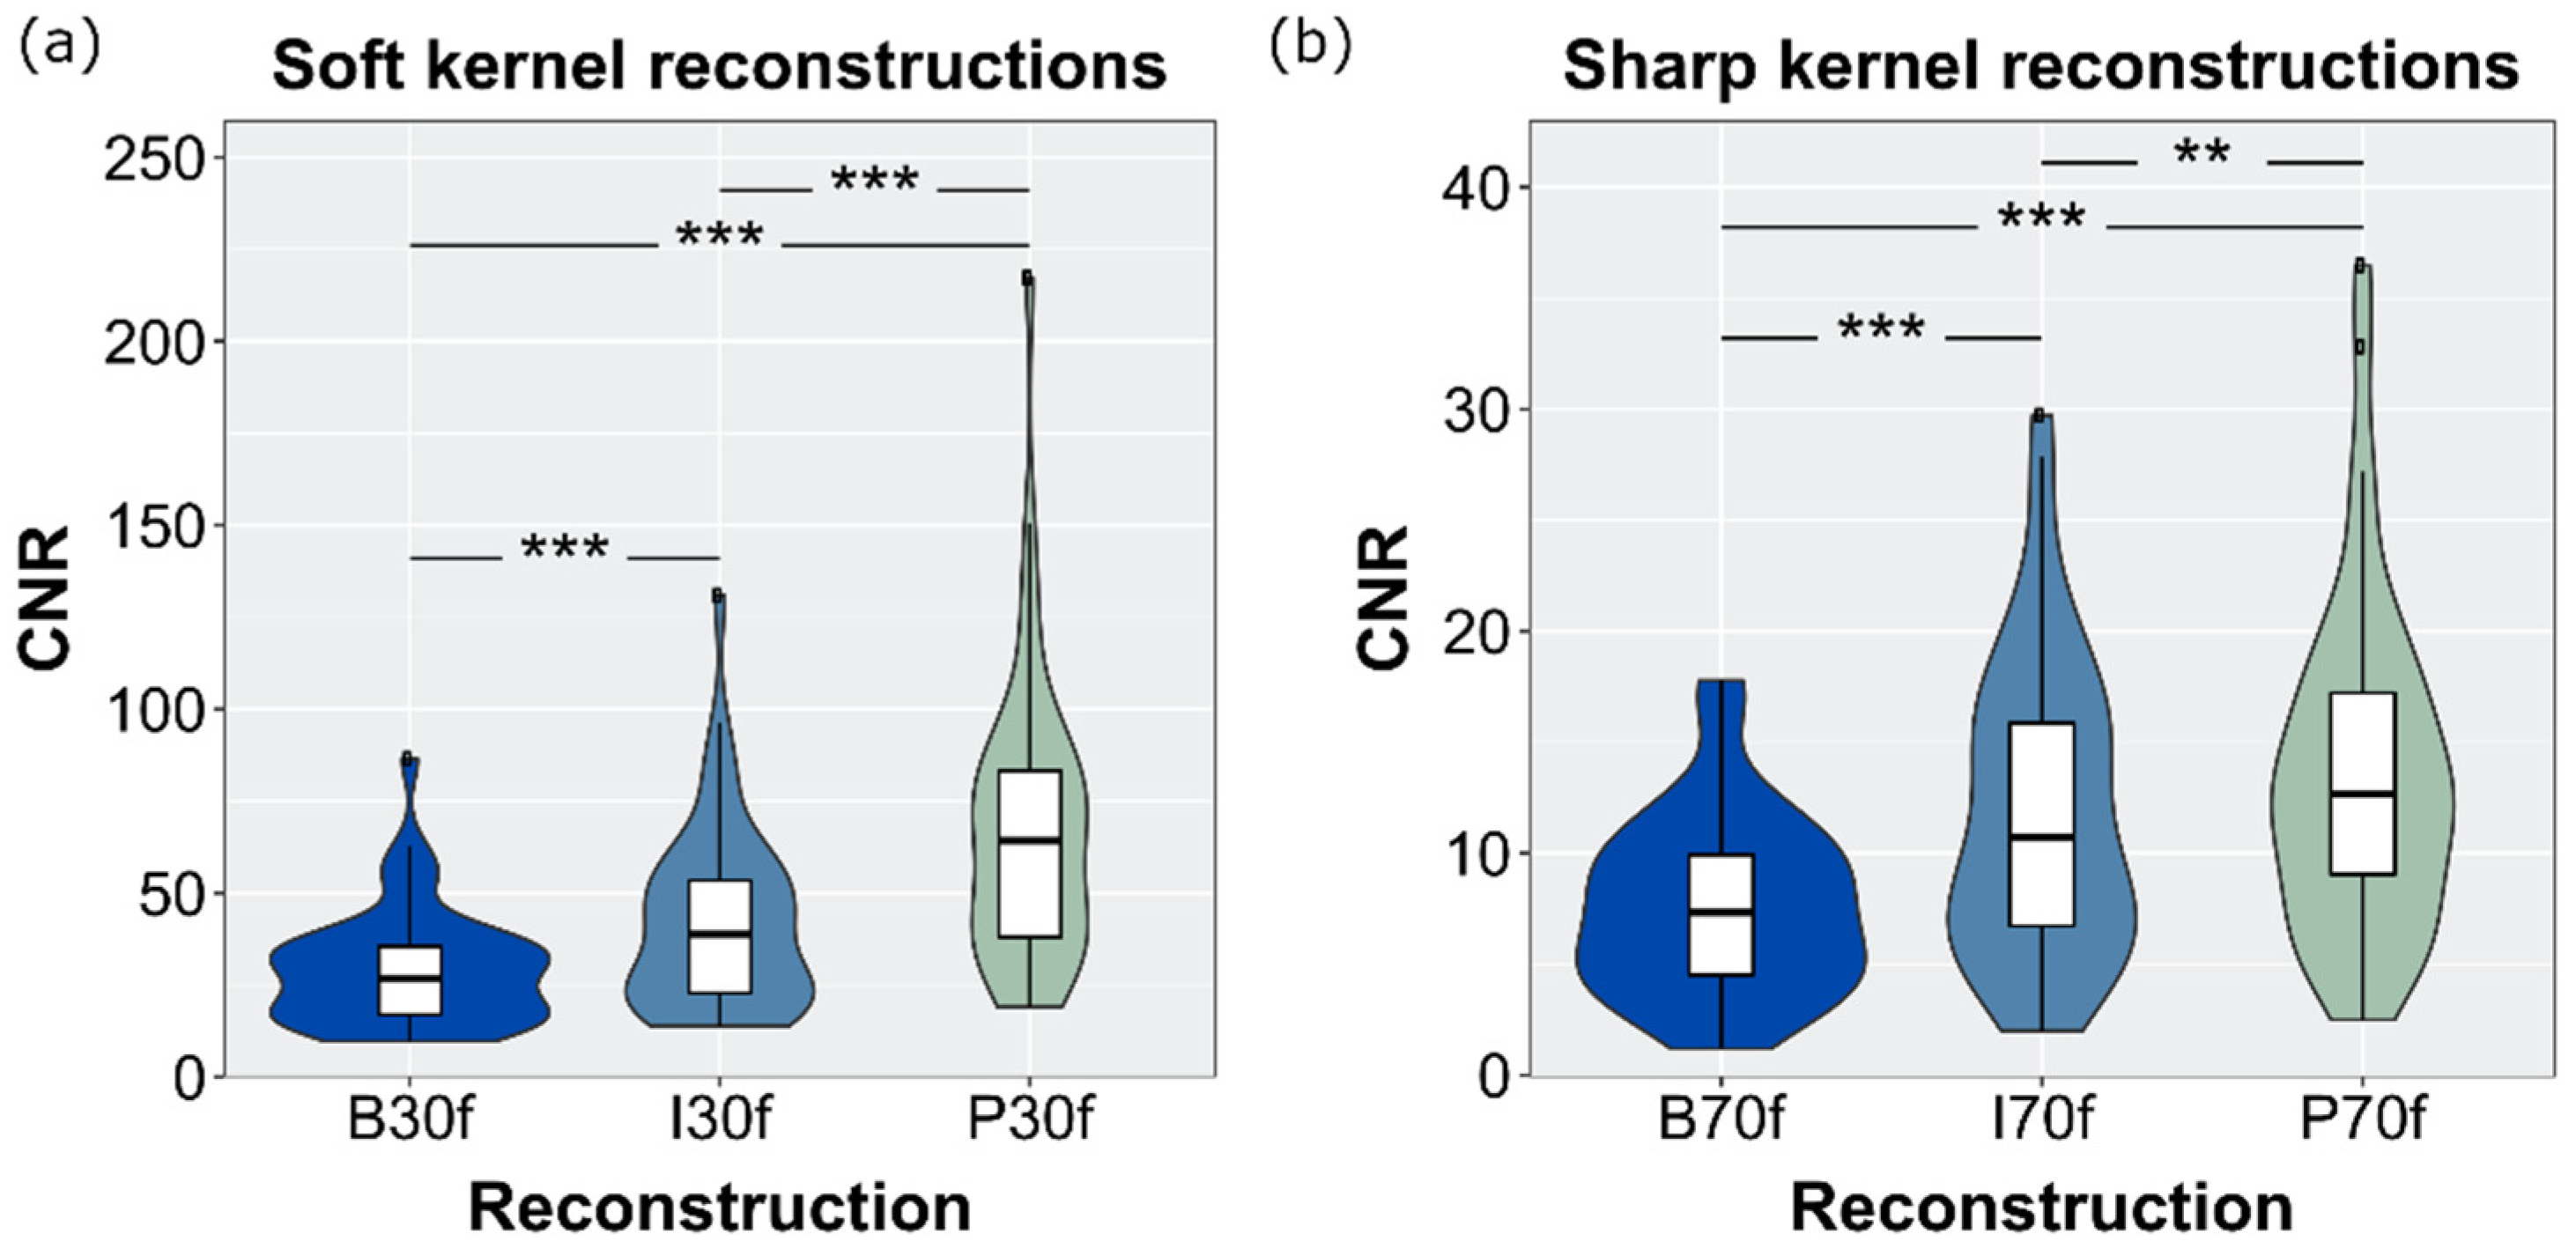

3.6. SNR and CNR

| Image Noise | B | I | P |

| Air (sharp) | 77.5 ± 15.9 | 49.4 ± 13.5 | 28.5 ± 14.3 |

| Bone (sharp) | 212.3 ± 40.1 | 143.0 ± 31.1 | 124.0 ± 20.7 |

| Liver (soft) | 38.2 ± 7.7 | 26.2 ± 5.0 | 20.3 ± 4.8 |

| Muscle (soft) | 31.6 ± 5.6 | 21.7 ± 3.9 | 14.5 ± 2.6 |

| Spleen (soft) | 34.5 ± 7.0 | 23.4 ± 4.8 | 16.4 ± 4.1 |

| Fat (soft) | 29.4 ± 5.6 | 20.4 ± 4.2 | 12.8 ± 3.1 |

| Statistical differences (p < 0.001) among all reconstructions within one ROI. Abbreviations: B: filtered back-projection, I: iterative reconstruction; P: PixelShine. | |||